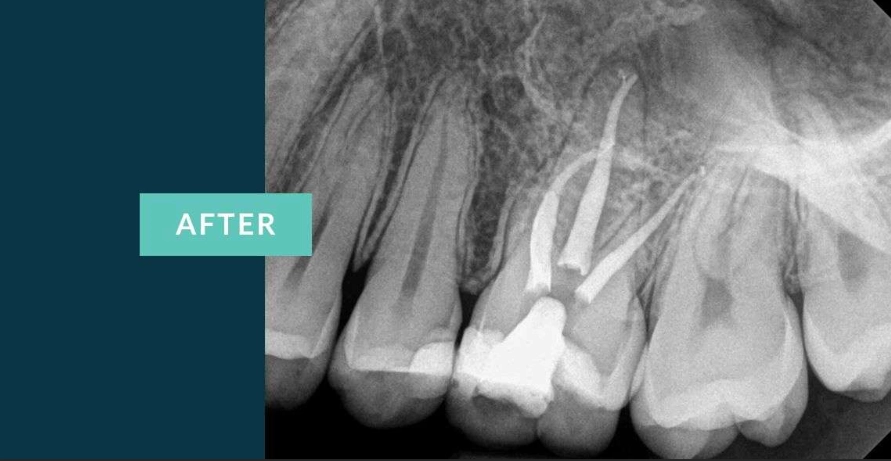

Access and Cleaning: A small opening is made in the top of the tooth. Using very fine files, the dentist removes the diseased pulp and meticulously cleans and shapes each canal. This is where the microscope is a game-changer. It allows the clinician to see intricate details, find hidden canals, and ensure no debris is left.

Disinfection and Filling: The canals are flushed with antimicrobial solutions. Once dry, they are filled with a rubber-like material called gutta-percha, sealed in place with a biocompatible cement. The goal is to hermetically seal the space to prevent re-infection.

The Critical Step Almost Everyone Forgets After the Root Canal

Here's the part most blog posts gloss over, and it's the single most important factor for long-term success: the final restoration. A root canal-treated premolar is more brittle than a vital tooth. It's like a hollowed-out tree branch—structurally weaker.

For almost every premolar, you will need a dental crown. This cap encases the entire tooth, protecting it from fracture and restoring its function for chewing. Sometimes, if a lot of tooth structure is missing, a post may be placed inside the canal to help anchor the crown. Don't delay this step. Schedule your crown appointment within a few weeks of the root canal.